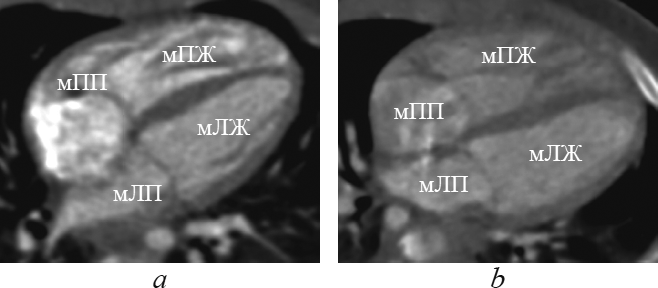

В данной статье приведены результаты анализа данных рентгеновской компьютерной томографии с внутривенным болюсным введением контрастного вещества детей с транспозицией и корригированной транспозицией магистральных артерий путем последовательного построения многоплоскостных реформаций, ориентированных на оси сердца. Из 148 детей со сложными врожденными пороками сердца и магистральных артерий транспозиция магистральных сосудов встречалась у 13 пациентов (в возрасте от 1 до 144 дней жизни; 9 — мужского пола, 4 — женского пола), корригированная транспозиция магистральных сосудов — у 4 пациентов (в возрасте от 6 мес. до 15 лет 6 мес.; 2 — мужского пола, 2 — женского пола). В статье подробно описаны анатомические характеристики, на основе которых определяется морфология каждой камеры сердца, и реформации, в которых они оцениваются. В статье приводится сравнительная характеристика структур сердца и магистральных артерий при транспозиции и корригированной транспозиции магистральных артерий в каждой отдельно взятой реформации, ориентированной на оси сердца. По результатам анализа последовательно построенных реформаций, ориентированных на оси сердца, указаны и проиллюстрированы характерные анатомические признаки транспозиции и корригированной транспозиции магистральных сосудов. Установлено, что из перечня предлагаемых реформаций, ориентированных на оси сердца, характерные анатомические признаки транспозиций достоверно определяются в следующих реформациях: по длинной оси приносящего тракта правого желудочка; левых камер сердца; приточных отделов желудочков; по короткой оси на уровне магистральных сосудов. Многоплоскостные реформации, ориентированные на оси сердца, на основе данных КТ-ангиокардиографии позволяют дать полную и точную анатомическую оценку сердца и магистральных сосудов, что важно при планировании оперативного вмешательства при врожденных пороках сердца.